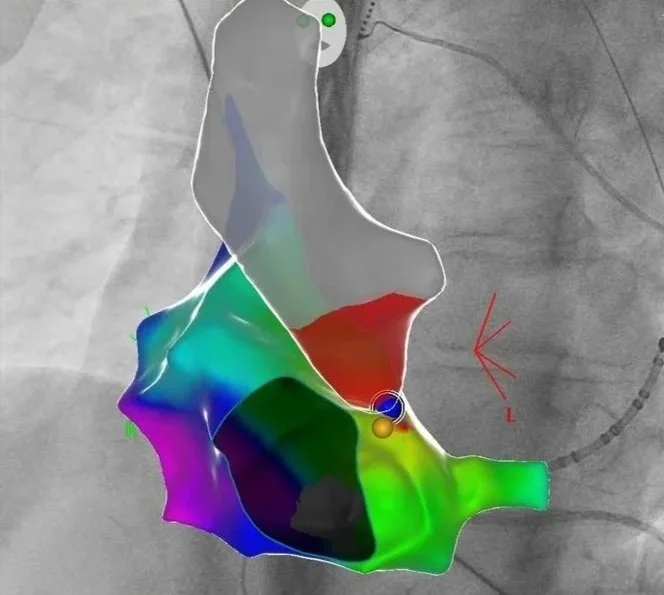

3D Navigation einer akzessorischen Leitungsbahn WPW

Im Rahmen spezieller elektrischer Herzkatheteruntersuchungen können wir die Reizleitungseigenschaften des Herzens untersuchen - hierzu werden über die Leiste elektrische Herzkatheter am Herzen positioniert und über Provokationsmanöver die Herzströme vermessen. Auftretende Rhythmusstörungen können unter Verwendung eines hochmodernen 3D-Navigationssystems mit Röntgen-Bildfusion genau kartiert werden, und können prinzipiell auch Strahlen- und Kontrastmittelfrei erfolgen. In gleicher Sitzung kann dann auch die Verödung der Herzrhythmusstörung erfolgen.